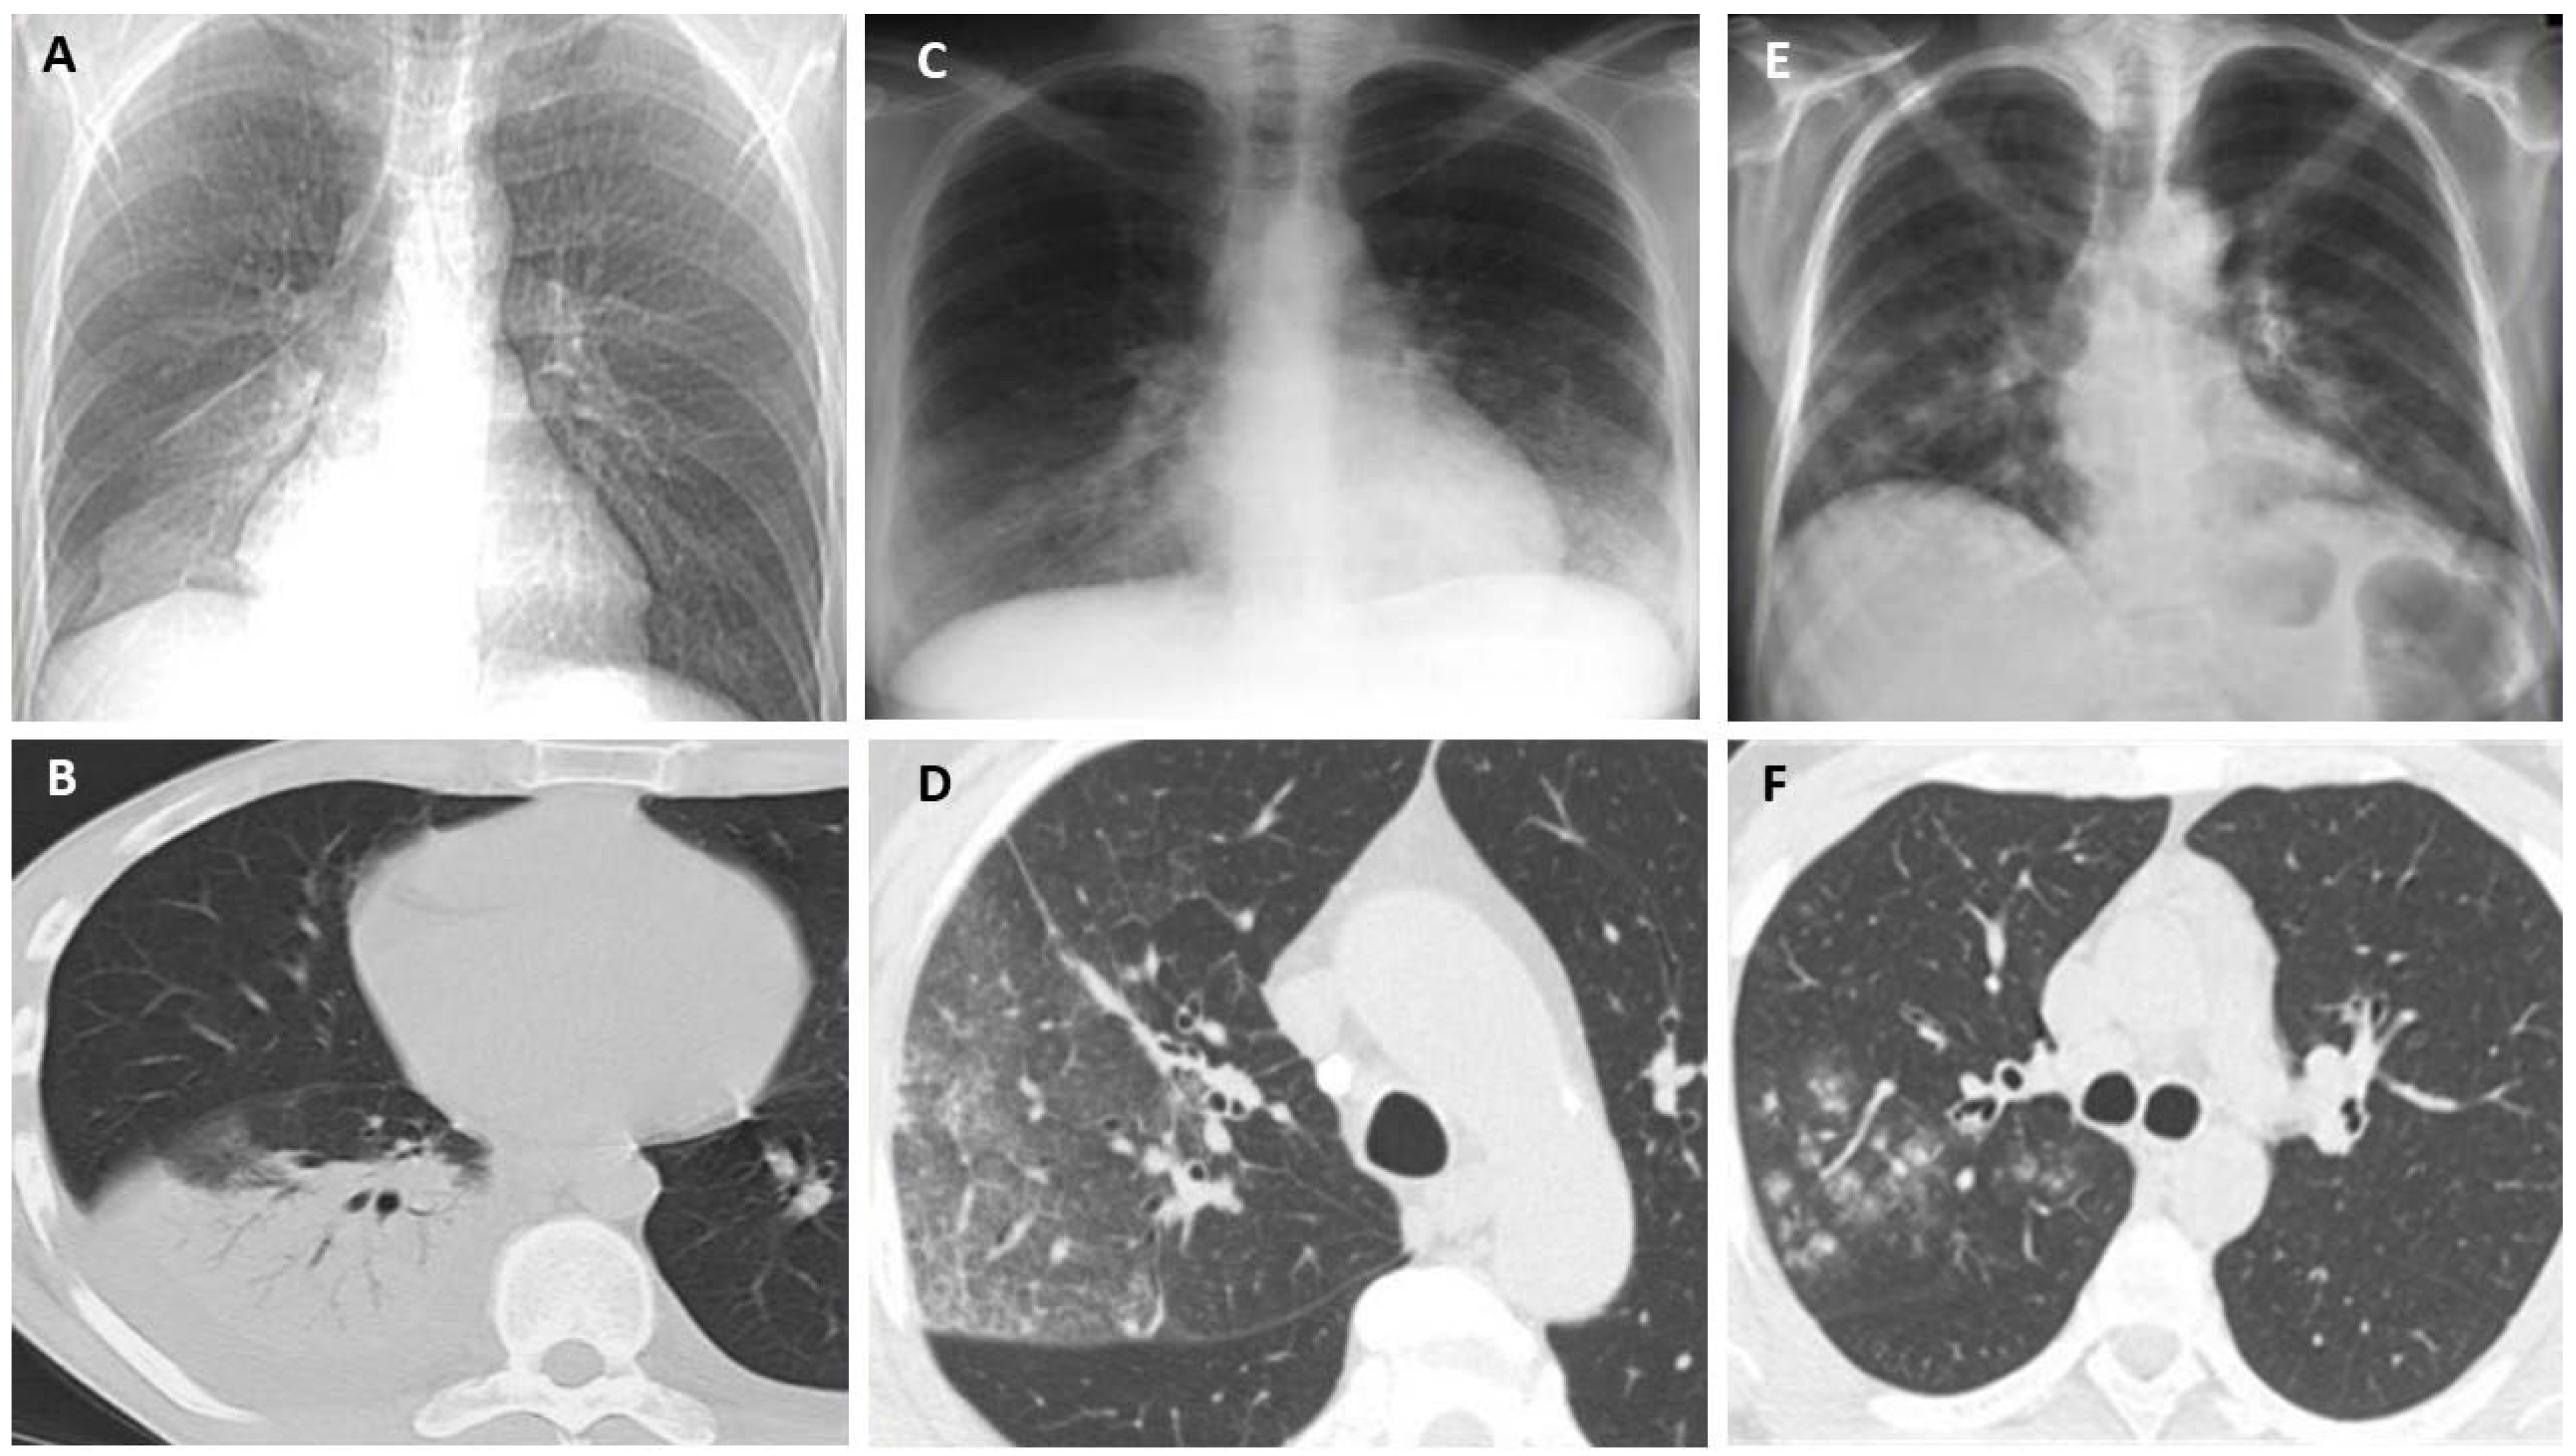

- D’Angelo, A.; De Simone, C.; Pagnottella, M.; Rossi, S.; Pepe, R.; Ruggieri, G.; Cocco, G.; Schiavone, C. A Case of Legionella pneumophila Evaluated with CT and Ultrasound. J. Ultrasound 2017, 20, 243–245. [Google Scholar] [CrossRef] [PubMed]

- Nakanishi, M.; Shiroshita, A.; Nakashima, K.; Takeshita, M.; Kiguchi, T.; Yamada, H. Clinical and Computed Tomographic Features of Legionella Pneumonia with Negative Urine Antigen Test Results. Respir. Investig. 2021, 59, 204–211. [Google Scholar] [CrossRef] [PubMed]

- Kim, K.W.; Goo, J.M.; Lee, H.J.; Lee, H.Y.; Park, C.M.; Lee, C.H.; Im, J.-G. Chest Computed Tomographic Findings and Clinical Features of Legionella Pneumonia. J. Comput. Assist. Tomogr. 2007, 31, 950–955. [Google Scholar] [CrossRef]